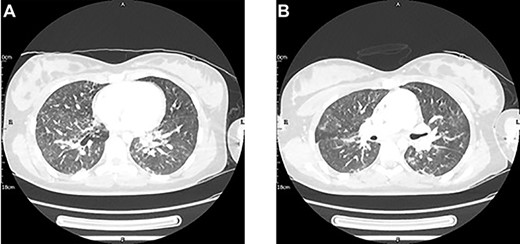

On Day 2, she deteriorated with new fluctuating consciousness in addition to a persistent oxygen requirement and poor UO. A head CT showed no new pathology, but a thoracic CT showed infective features (Fig. 1). A further negative SARS-COV-2 test was returned, so a course of intravenous antibiotics was prescribed. Half a day later, her GCS stabilized.

A thoracic CT with contrast conducted 2 days post-injury showed new mild bilateral peri-bronchial wall thickening and bilateral patchy ground-glass changes with early nodular consolidative changes. These features were thought to be in keeping with an infection, either aspirational pneumonia or COVID-19. Pulmonary contusions could have also contributed to the pulmonary changes given the clinical context.

Imaging can be a helpful adjunct to clinical assessment of FES. Thoracic CT has shown diagnostic potential, with patchy ground-glass opacities with areas of sparing plus smooth interlobular septal thickening a consistent radiological features in FES [1, 2]. However, an initial negative CT does not rule out FES, and one must consider the consequences of repeated radiological exposure in a young female patient such as ours [2]. In addition, specificity is currently hindered by COVID-19. More promising is cerebral MRI, with the presence of dispersed hyperintense lesions on T2-weighted images found to be sensitive for FES in patients with cerebral involvement, even in those with a normal CT like our patient [2, 5, 6]. Cerebral involvement is not reliant on paradoxical emboli, and radiological signs can appear as early as 4 h post trigger [2, 5–7].